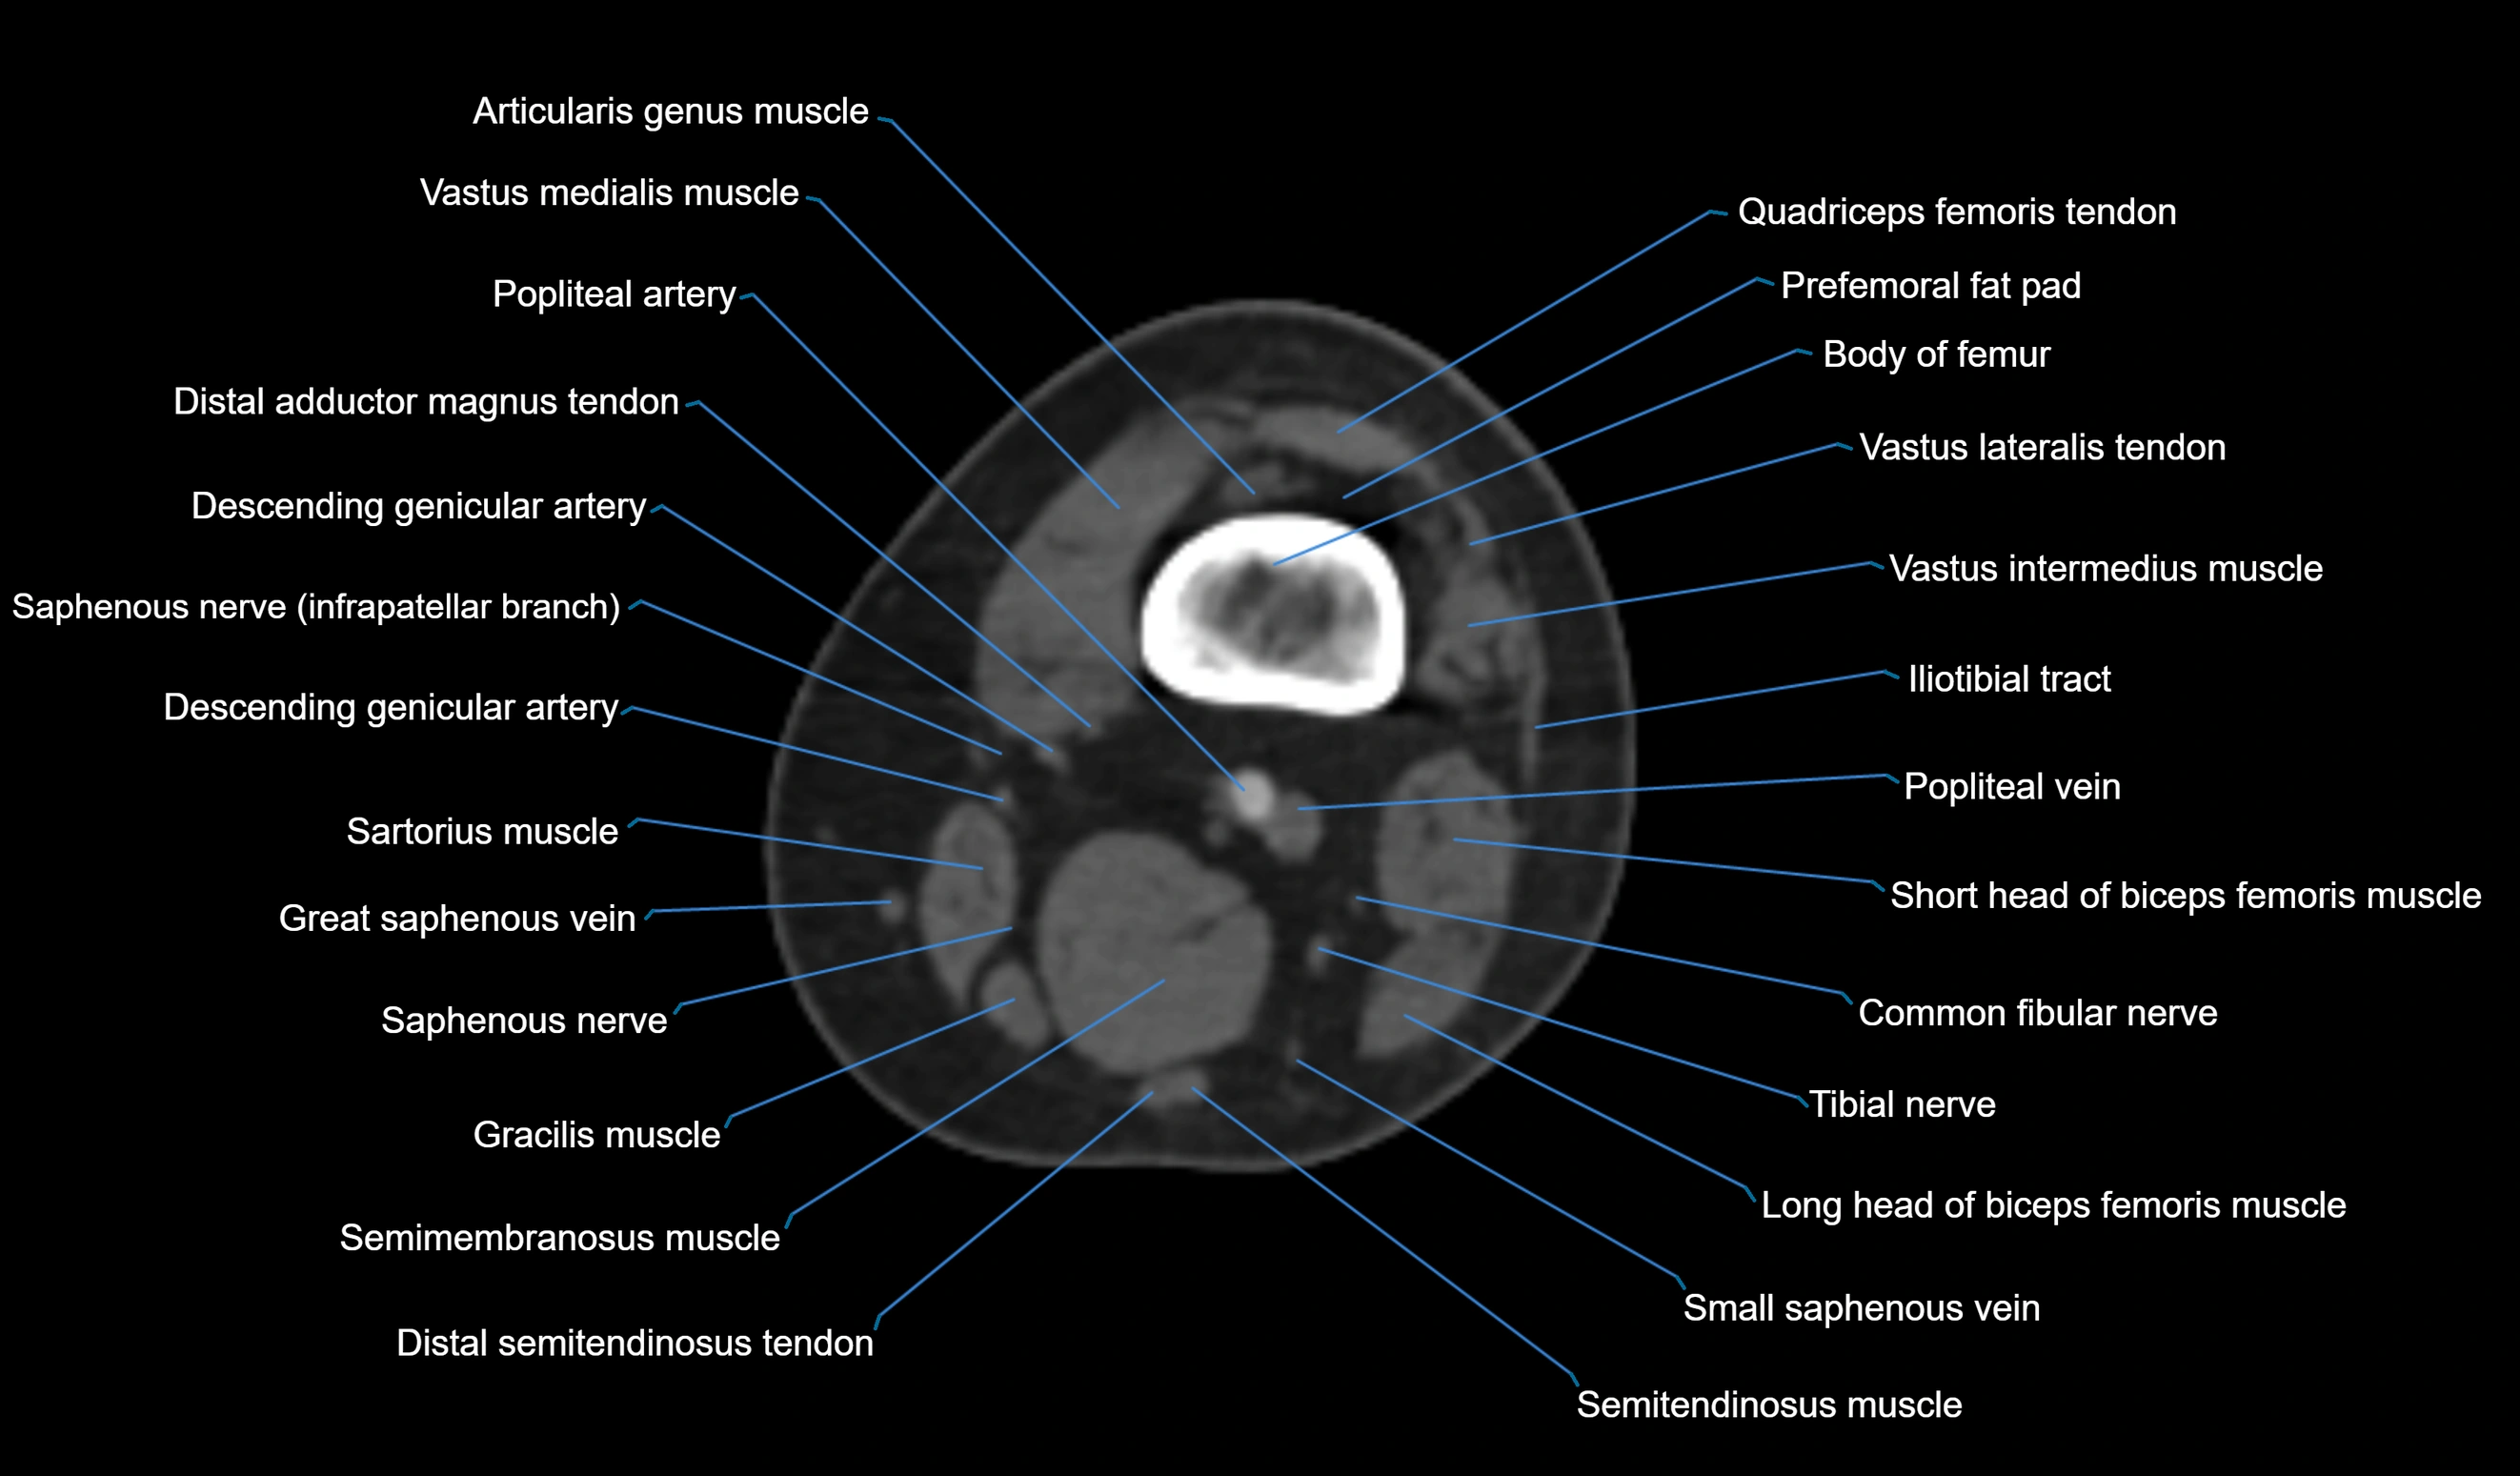

- Body of femur

- Common fibular nerve

- Distal adductor magnus tendon

- Distal quadriceps femoris tendon

- Distal semitendinosus tendon

- Distal vastus intermedius tendon

- Distal vastus lateralis tendon

- Gracilis tendon (Distal)

- Popliteal artery

- Popliteal vein

- Popliteus tendon

- Prefemoral fat pad

- Saphenous nerve

- Sartorius muscle

- Semimembranosus muscle

- Semitendinosus muscle

- Small saphenous vein

- Tibial nerve

- Vastus lateralis muscle

- Vastus medialis muscle

- great saphenous vein